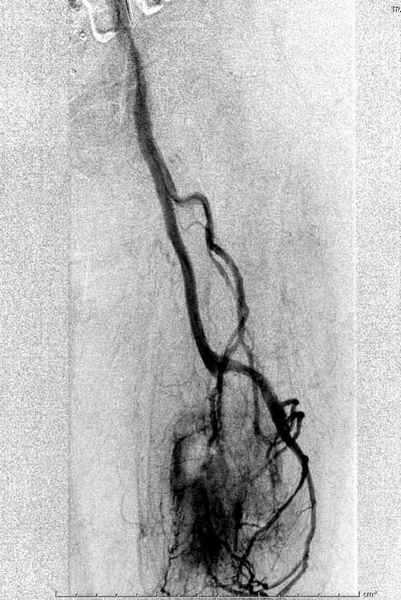

В зависимости от характера опухоли некоторые патологические переломы имеют риск кровотечения во время операции. Множественные литературные данные подтверждают, что надо проявить осторожность при интрамедуллярном остеосинтезе при неизвестных опухолях, особенно где имеется подозрение на Renal Cell Carcinoma. (RCC- hypernephroma) http://www.bonetumor.org/tumors/pages/page64.html

Для предупреждения кровотечения во время рассверливания, за день до операции провели эмболизацию сосудов питающий метастаз. http://radiology.rsnajnls.org/cgi/reprint/150/3/673.pdf (7-11, 12-15-16)